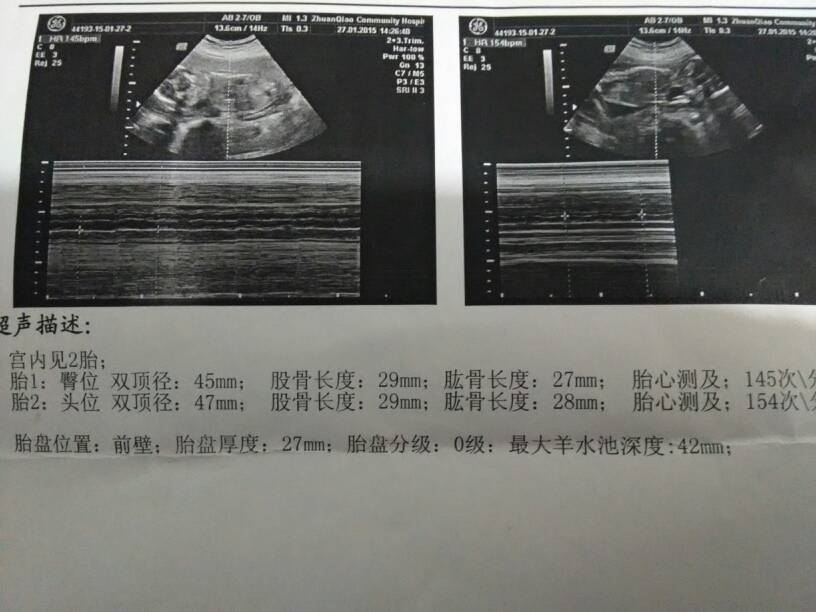

有朋友能看懂是男孩女孩吗? 有朋友能看懂是男孩女孩吗? 点击展开 136*****509_O5SV 2015-01-27 20:21 为您推荐: 其他回答 双胞胎。。。。 诺言妈妈™ 2015-01-27 22:38 可能是龙凤胎啊! 东京的樱花 2015-01-27 22:37 嗯,儿子就儿子啰,都是自己孩子。 守望幸福@ 2015-01-27 21:21 我还真希望自己可以怀一对双胞胎儿子,就不用再生多一次。 守望幸福@ 2015-01-27 21:19 你养有男孩了吧?一对双胞胎儿子不好吗? 守望幸福@ 2015-01-27 21:17 加载更多 相关问题 有朋友知道哪里能查男孩女孩 唐筛报告,谁能看懂,是男孩女孩 刚做了大畸形筛查,医生说了句:目前能看到的都是正常的!有没有能看懂B超的,男孩女孩能看出来么?